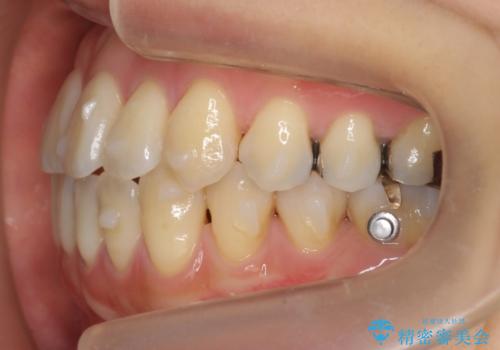

前歯のがたつき 若干受け口 インビザラインで

治療症例の内容

- 前歯のねじれおよび下の前歯が前に出ていることを気にして来院。

インビザラインで治療をおこないました。

前歯のねじれもなおり、比較的短期間でご満足いただけました。

部分矯正コースでしたので左下67の段差は特に治しておりません。

右下567及び左下6の虫歯治療も一緒に行っています。